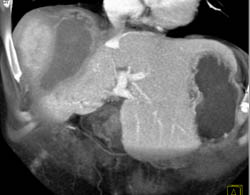

Focal Nodular Hyperplasia (FNH)